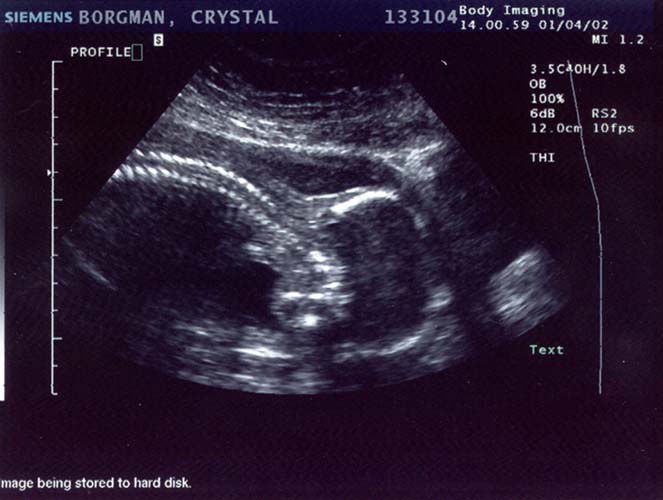

1/4/02

Well

it's a stubborn little bugger. The ultrasound technician

tried and tried so hard to find out the sex, bless her

heart. At the beginning she thought maybe she saw something

that would indicate it was a boy, but she wasn't even

remotely sure by any means. She said she'd check again

later and wasn't confident in the least bit that it was

actually a boy.

Later came, and

went. Baby had its legs crossed the whole time. She

also said there was a lot of umbilical cord around the

legs, so what she saw earlier may have been the cord

too. I drank a full 12 ounces of Coke before I went

in, hoping that would get the baby moving. It was moving

alright, but apparently not enough. The tech tried pushing

on my belly at all angles to get the baby to move but

it would not budge. Well I have to say I'm pretty bummed.

I've been holding out on buying clothing and stuff...

but now I know what I need to get: a whole shit-load

of gender neutral stuff. No, we will not be getting

another ultrasound so this is it until the baby's born.

On a happier note,

everything checks out ok. We saw 4 chambers in the heart

and it was beating away happily at about 142 bpm, she

said. All organs appeared to be present and looking

good. The big shocker was that the estimated weight

was 1 pound, 11 ounces. OUCH! All my pregnancy calendars

say it should still be under a pound... but maybe their

estimate was off. That does, however, help explain my

6-pound weight gain in the last month. At any rate,

all the measurements were normal and my due date remains

unchanged.

Ultrasound Pictures:

Profile with head

on the right, facing down (towards my back), spine clearly

visible

Large

- 663x550 pixels / 66.1K

Small

- 332x250 pixels / 28.2K

Leg (foot is on

the right, pointing up)

- 682x500 pixels / 68K

- 341x250 pixels / 28.8K